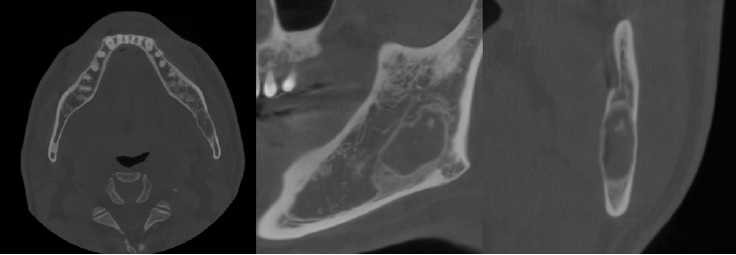

Fig. 1.

Panoramic radiograph shows a radiolucent lesion of irregular shape and relatively well-defined margins beneath the periapical area of the left mandibular third molar.

A 52-year-old male was referred to the Gangneung-Wonju National University Dental Hospital, from a local dental clinic for evaluation of a lesion in the left mandibular angle and ramus. The lesion had been identified on a panoramic image obtained for the extraction of the left mandibular second molar, five days prior to presenting to our hospital. Clinical examination, including both intraoral and extraoral assessments, revealed no remarkable findings.The patient underwent a panoramic radiograph and cone-beam computed tomography (CBCT). The panoramic radiograph showed an ovoid, well-demarcated radiolucency with irregular contour, and internal lytic change beneath the periapical area of the left mandibular third molar region (Fig. 1). CBCT demonstrated a radiolucent lesion with a well-corticated margin and subtle internal calcified foci. Generalized sclerotic changes in the adjacent cancellous bone and thinning of the bucco-lingual cortex were noted, with mild expansion of the lingual cortex due to the lesion (Fig. 2). Anatomically, the lesion lay inferior to the mandibular canal and outside the tooth-bearing alveolus, which argued against an odontogenic origin. Collectively, these features were interpreted as a radiolucent lesion with surrounding sclerosis. Routine laboratory tests (L30 clinical chemistry panel) revealed elevated glucose (135 mg/dL) and total cholesterol (233 mg/dL), while all other parameters were within normal limits. Based on the clinical and radiographic findings-posterior mandibular location, well-defined unilocular radiolucency with a pronounced adjacent sclerotic change, cortical thinning with mild expansion but without periosteal reaction or cortical breach, and non-odontogenic position—the working differential favored non-ossifying fibroma, with a simple bone cyst considered less likely.Histopathological analysis of the decalcified mandibular specimen revealed a mass predominantly composed of brown fat cells. Within the lesion, focal areas of cholesteatoma-like formation and numerous variably sized bony particle deposits were identified. Tumor cells exhibited eosinophilic granular cytoplasm with eccentric nuclei, consistent with adipocytic differentiation. Notably, the majority of the mass consisted of polygonal brown fat cells displaying multiple cytoplasmic vacuoles (Fig. 3). Based on the imaging appearance, the differential diagnosis favored non-ossifying fibroma, with simple bone cyst considered less likely. Intraosseous hibernoma was not initially suspected and was confirmed postoperatively by histopathologic examination. Overall, the findings supported a diagnosis of a lesion with extensive brown fat cells proliferation and secondary changes including bony particle deposition and cholesteatoma-like formation. These findings established the final diagnosis of intraosseous hibernoma. The patient has been followed periodically, and a 7-month postoperative panoramic radiograph and CBCT showed new bone formation along the superior, inferior, and lingual aspects of the postoperative defect consistent with healing, without evidence of recurrence (Fig. 4).